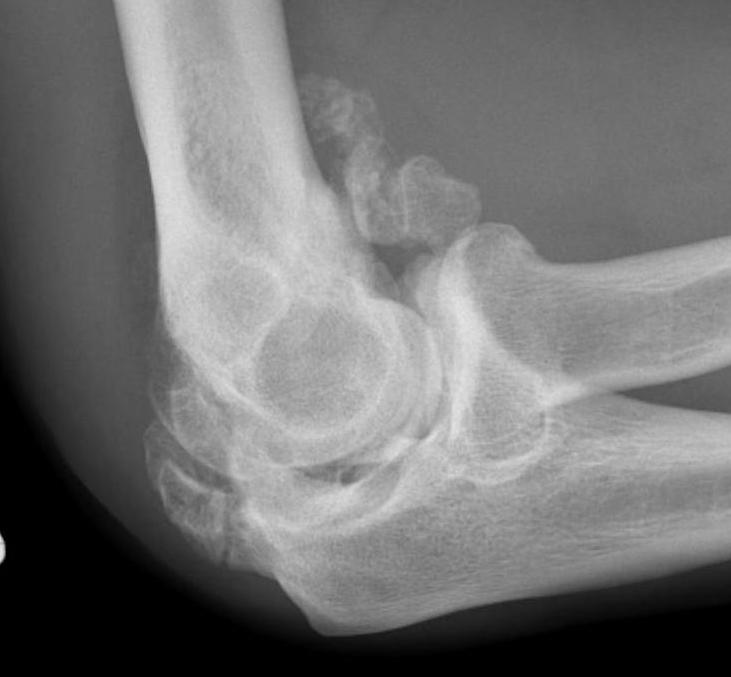

Xray

Radio-ulna synostosis

Mature bone

- smooth well demarcated edges on xray